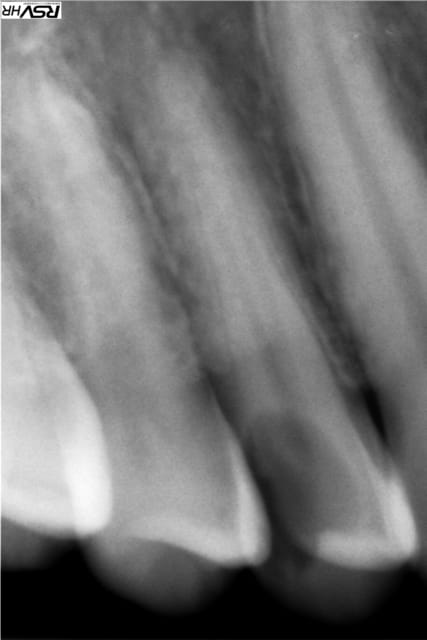

Si quelqu'un peut me renseigner sur cette image sur la 46 ?

Deuxième incidence pour vérifier la localisatio 3D de cette image.

Si c'est dans la 46, tu peux tout imaginer: malformation, résorption interne évolutive ou non, etc...

ça transpire la résorption !

j ' ai eu un cas similaire sur une 36. La résorption avait perforé la racine distale -> hémisection.

Cas quasi identique sur une 36 femme environ 35 ans.L'image était visible depuis quelques années mais récemment la dent était devenue sensible.Fait l'endo hier et confirmation de la résorption interne.Je te conseille de faire l'endo au plus vite car la résorption est déja bien avancée.

c'est une image très très curieuse

ca ne resseble pas à une resorpion interne, parceque celles-ci sont toujours centripète et qu'on voit bien la séparation avec la pulpe

l'aspect de la dentine est bizarre au niveau de la couronne et ajoute au mystère

à mon avis il s'agit d'une resorption externe vestibulaire ou linguale et un sondage devrait te permettre de conirmer le diagnostic si tu n'as pas de 3D

Ca ressemble plus a une résorption externe qu'interne

J'espère que ces radios seront plus claires.

Bon état dentaire, sauf énorme carie sur 14, et cependant, est venu consulter pour une douleur sur 45-46.

Pour bien vérifier, j'ai pris une radio de 46.

J'ai sondé en sous gingival et je n'ai rien trouvé.

C'est quand même bizarre cette zone claire qui suit le canal à distance.

L'ensemble de la dentine me semble un peu suspect.

Je vais dévitaliser la 14, et mettre sous surveillance la 46.

Et voir si la douleur ressentie au niveau 45-46 reste toujours présente.

dent in dentis